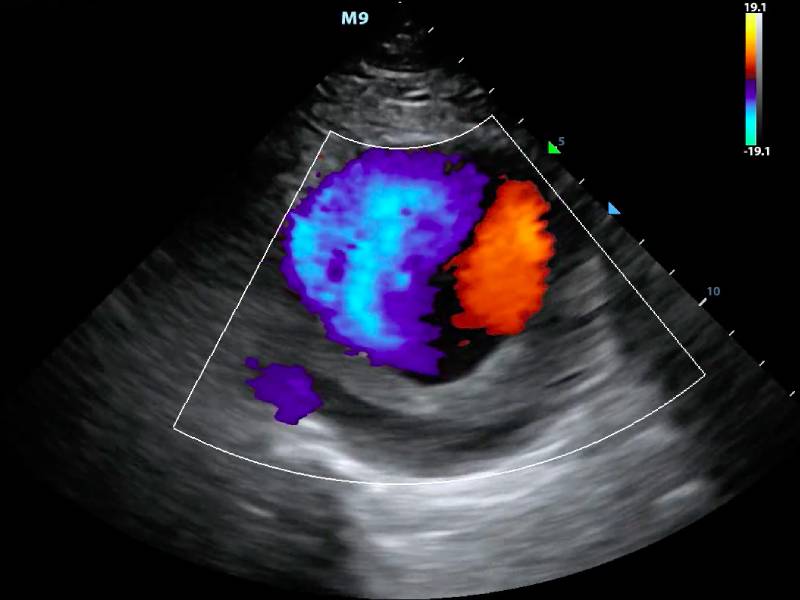

For many like Meena, the term "Colour Doppler Scan" may sound daunting. But in reality, this advanced imaging test is a non-invasive, safe, and crucial tool for diagnosing blood flow issues. Unlike traditional ultrasounds, the Colour Doppler uses sound waves to create color images of blood flow within the arteries and veins. This allows doctors to detect blockages, clots, and other vascular abnormalities with precision.